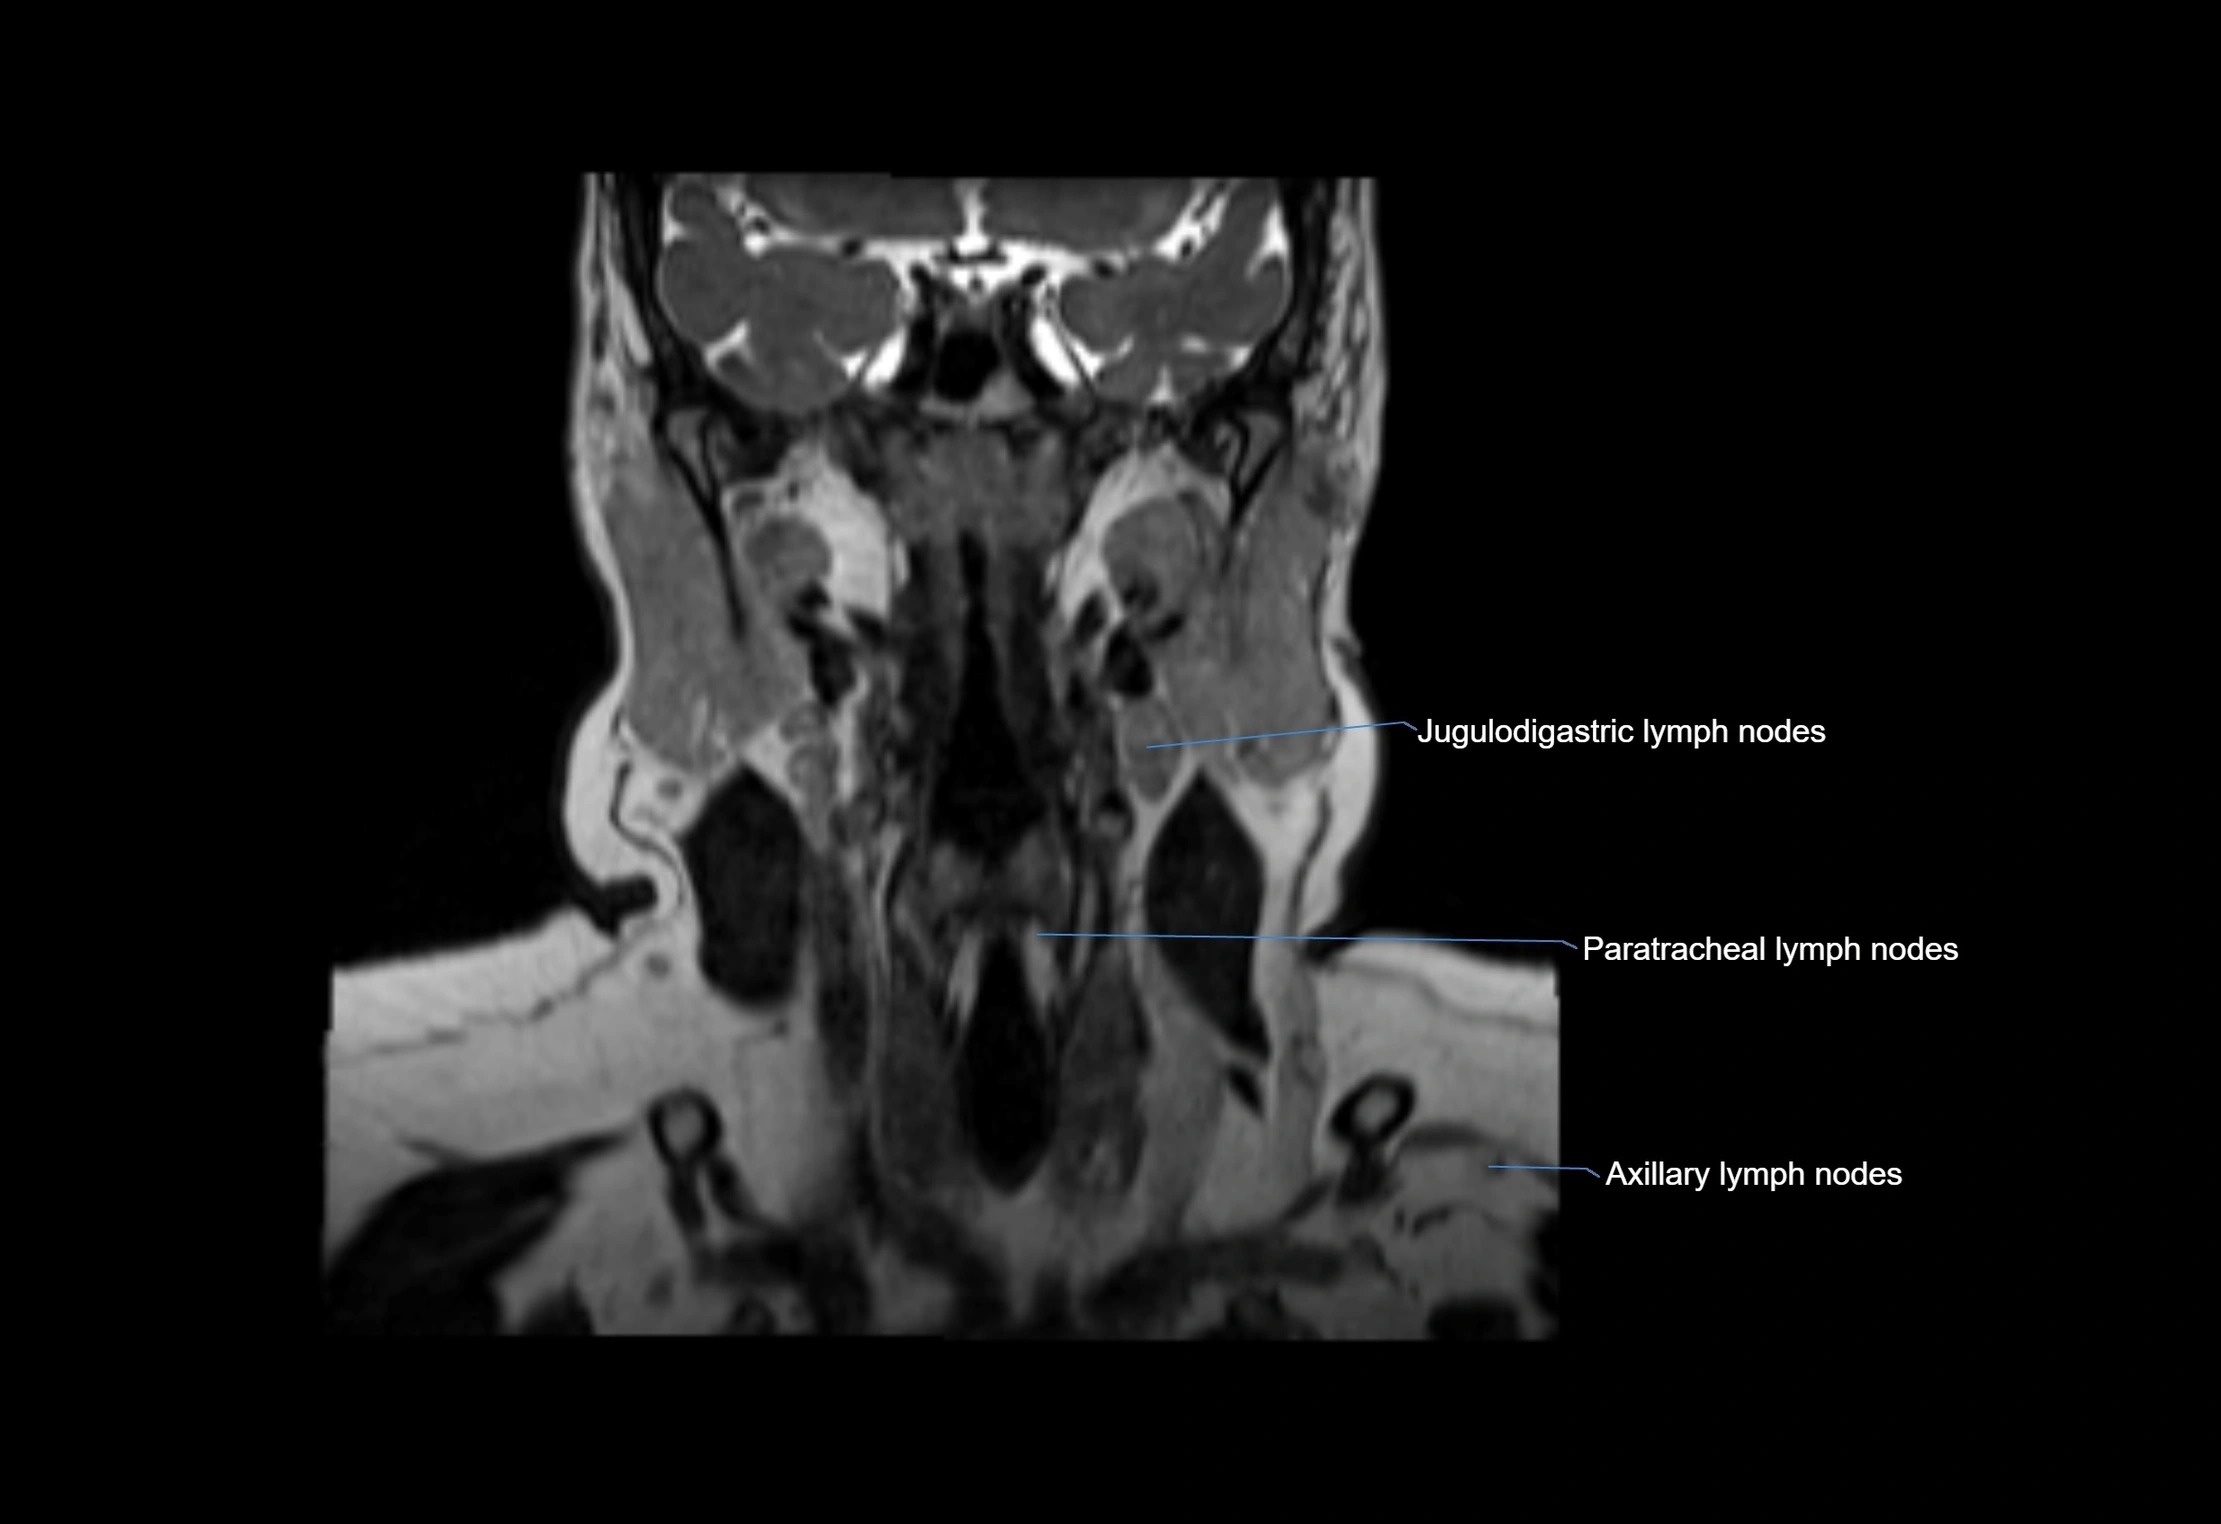

Accessory lymph nodes

Accessory lymph nodes are small, secondary lymph nodes located along the main facial and cervical lymphatic chains, often adjacent to primary lymph nodes, such as preauricular, submandibular, or occipital nodes. They are typically less than 5 mm in diameter, embedded within subcutaneous fat or connective tissue, and may be variable in number and location. These nodes provide additional filtration and immune surveillance for lymph collected from the face, scalp, and neck regions. Accessory lymph nodes are usually non-palpable in healthy individuals but may enlarge in response to infection, inflammation, or metastasis, making them clinically significant.

Location

• Found along primary lymph node chains, including preauricular, submandibular, parotid, and occipital regions

• Embedded in subcutaneous fat or superficial fascia, often lateral or posterior to primary nodes

• Variable in number; may occur unilaterally or bilaterally, depending on individual anatomy

MRI Appearance

T1 Post-Contrast (Gadolinium-enhanced):

• Normal nodes may show mild, homogeneous enhancement

• Inflamed or metastatic nodes demonstrate marked homogeneous or heterogeneous enhancement, highlighting the cortex and fatty hilum

• Post-contrast imaging helps detect early metastasis, infection, or inflammatory changes

CT Appearance:

• Nodes appear as small, soft tissue density structures embedded in subcutaneous fat near primary lymph nodes

• Surrounded by air in adjacent facial cavities or normal soft tissue, providing natural contrast

• Enlarged or pathological nodes appear as well-defined or irregular soft tissue masses

• CT is particularly useful for preoperative assessment, infection evaluation, or detection of metastatic spread